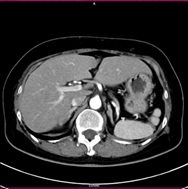

単純CT画像          造影CT画像          MPR画像